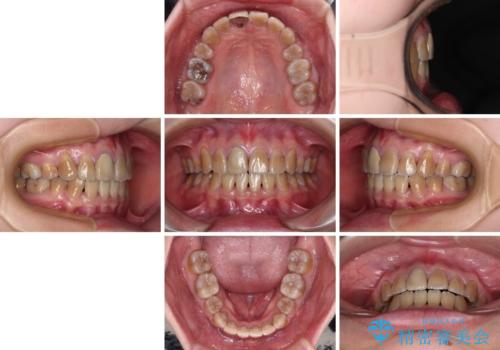

八重歯とクロスバイト 目立たないワイヤー装置での抜歯矯正

- 八重歯や前歯のデコボコを気にして来院された患者様です。

歯列が前方に傾斜しており、デコボコが強かったため、上下左右第一小臼歯4歯を抜去し、ワイヤー装置による矯正治療を行うこととしました。

上下の正中がずれていましたが、抜歯矯正であったので、極力正中位置を合わせるように治療を進めて行きました。

顎間ゴムの使用などにより、正中位置を改善することができました。